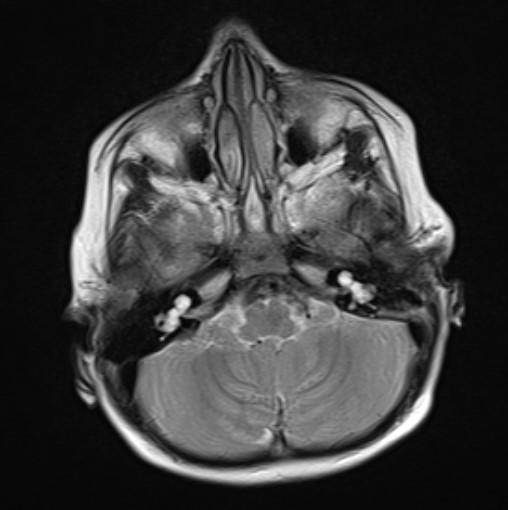

*2-year-old child with hearing loss.

Answer: Bilateral incomplete partition Type I (cystic cochleovestibular anomaly)

Axial MR and CT images show the cystic bilateral cochlea (red arrow) and the dilated cystic bilateral vestibule (yellow arrow). The vestibular aqueduct is normal in size.